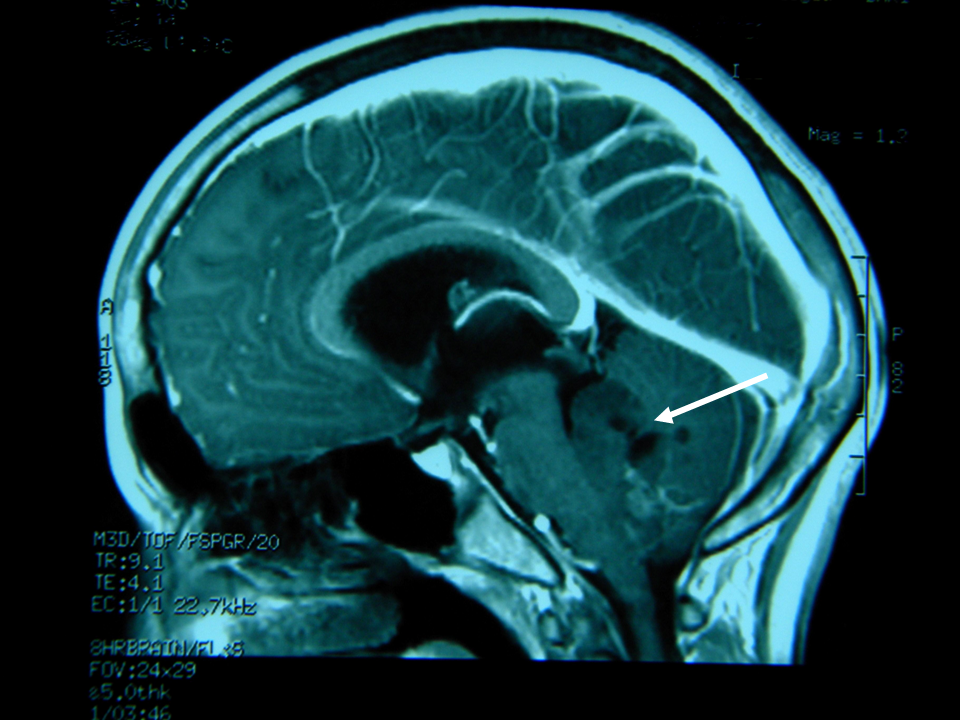

A fine maggio L. viene quindi ricoverato presso il nostro centro per vomito persistente e calo ponderale. L. ha 13 anni e 10 mesi e pesa 39,5 kg (< 10�); la madre riferisce un calo ponderale di circa 13 kg in 4 mesi. Vengono inizialmente formulate alcune ipotesi diagnostiche: RGE, esofagite eosinofila, gastrite Helicobacter pylori-positiva. L. viene sottoposto a una serie di esami di laboratorio e strumentali: le uniche alterazioni riscontrate sono rappresentate da una eosinofilia relativa, da un aumentato livello sierico di IgE e da una positivit� degli skin prick test per pollini di paritaria, acari della polvere e della farina, epitelio di cane e gatto; alla valutazione cardiologica viene rilevata una frequenza cardiaca di 65 bpm. Si decide di eseguire a una nuova EGDS che mostra reperti compatibili con esofagite da reflusso, antrite e reflusso duodenogastrico. Nel sospetto di una ulteriore componente psicogena o neurologica del vomito viene richiesta una valutazione neuropsichiatria infantile che rileva una spiccata deflessione del tono dell�umore necessitante di terapia con valproato, consiglia l�esecuzione di un ulteriore valutazione del fundus oculi e l�esecuzione di RM cerebrale. Il fundus oculi, eseguito nella stessa giornata, non mostra alterazioni patologiche. Alla RM viene evidenziata una neoplasia cerebellare mediana a livello del IV ventricolo (Figura 1 e Figura 2), con iniziale discesa delle tonsille cerebellari nel forame magno e sistema ventricolare sovratentoriale moderatamente dilatato con lievi segni di tensione liquorale; viene eseguita anche una scansione del rachide che evidenzia nodulazioni a livello del sacco durale di L5-S1-S2 da verosimile localizzazione secondaria per diffusione liquorale della neoformazione (Figura 3).

Figura 1. Scansione sagittale dell�encefalo in risonanza magnetica: neoplasia cerebellare mediana a livello del IV ventricolo.